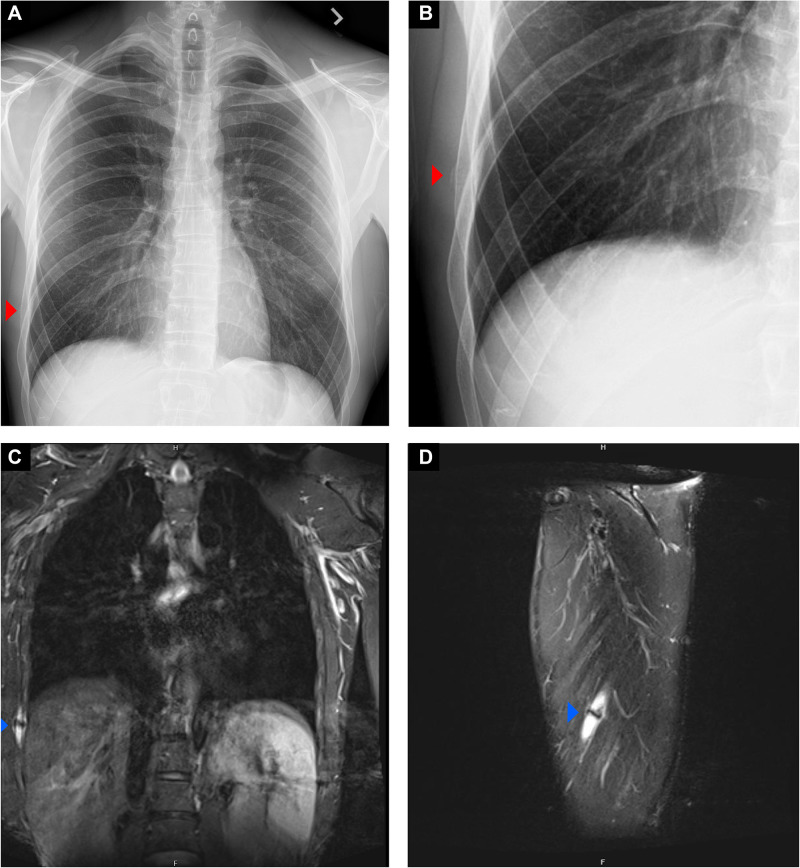

投球是一个复杂的动力学链式活动,需要从下半身,通过核心和躯干,最后通过手臂传递能量,以产生棒球的爆炸性加速度。因此,躯干肌肉组织和肋骨附着物从俯仰的后期翘起阶段通过减速产生了很大的力。重复的累积负荷和高的投球速度使职业投手面临肋骨应力性骨折的风险。考虑到潜在的长期恢复过程和高复发率,早期识别肋骨应力性损伤是优化护理的关键。识别躯干力量失衡、投球生物力学不佳(如骨盆旋转迟缓或不充分)以及可能对骨骼健康产生不利影响的代谢缺陷,对于加快安全回归和防止未来受伤至关重要。在这篇综述中,我们讨论了危险因素,损伤机制,典型的临床表现,诊断影像学表现,并提出了治疗和预防策略的右手投手肋骨应力性骨折。

Pitching is a complex kinetic chain activity requiring the transfer of energy from the lower body, through the core and trunk, and finally through the arm to generate explosive acceleration of the baseball. As a result, large forces are generated in the trunk musculature and rib attachments from the late cocking phase of pitching through deceleration. The repetitive cumulative load and high pitch velocities put professional pitchers at risk of rib stress fracture. Given the potential for a prolonged recovery course and high rate of recurrence, early recognition of rib bone stress injury is critical to optimize care. Identifying torso strength imbalances, suboptimal pitching biomechanics (such as late or inadequate pelvic rotation), as well as metabolic deficiencies that may adversely affect bone health are essential to expedite safe return to play and prevent future injury. In this review, we discuss risk factors, mechanism of injury, typical clinical presentation, diagnostic imaging findings, and propose treatment and prevention strategies for rib stress fractures in overhand pitchers.